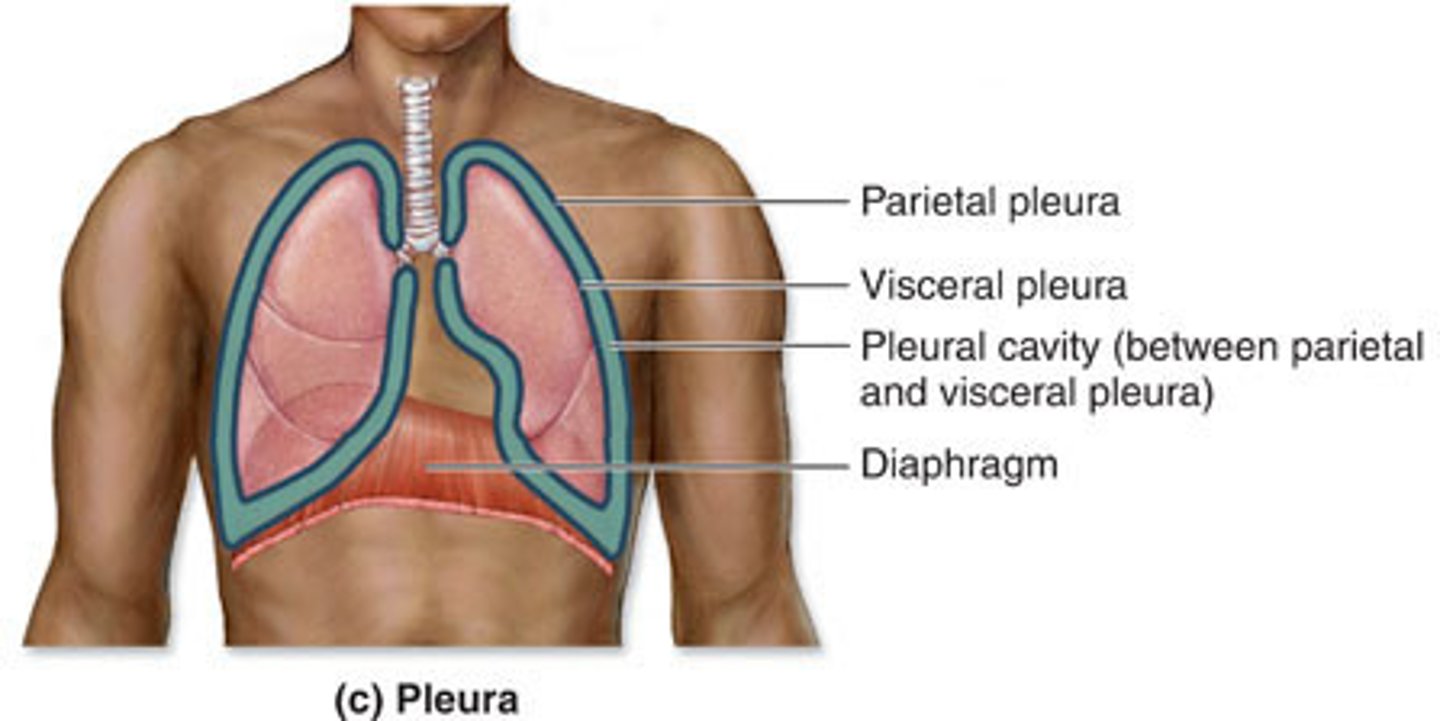

pleurae

parietal pleura

outermost layer of the pleura that connects to the thoracic wall, mediastinum, and diaphragm

visceral pleura

innermost layer of the pleura that is superficial to the lungs and extends into the lung fissures

pleural cavity

space between the visceral and parietal pleurae

pleural fluid

thoracic diaphragm